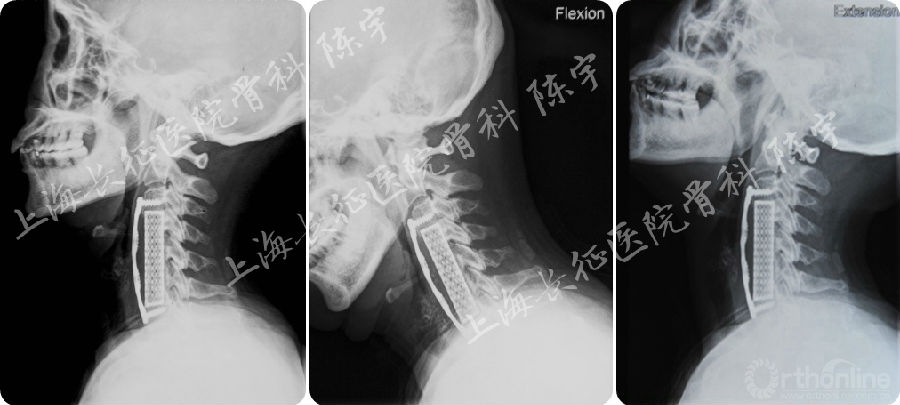

(2) K线在颈椎后纵韧带骨化的手术入路选择中的应用:K线是指C2和C7水平矢状径中点的连线,由日本学者首先提出并将其用于颈椎后纵韧带骨化手术入路的选择,骨化物未超过该线为K线(+),骨化物超过该线为K线(-),研究表明对于K线(+)患者选择后路手术的疗效明显优于K线(-)患者,K(+)患者在JOA评分的各项指标中,除了膀胱功能以外其他各项指标均获得明显改善, 而K线(-)组的患者只在上肢和下肢的感觉功能获得改善;此外,术中超声检查提示 K线 (-)患者后路减压后脊髓漂移不足,前方压迫仍然存在[4、5]。该例患者的骨化物超过K线,为K线 (-)患者,选择后路手术的疗效有限(图5)。